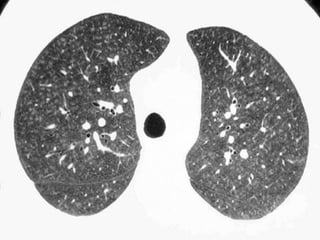

 A nodular pattern consists of multiple round opacities,

generally ranging in diameter from 1 mm to 1 cm

 Nodular opacities may be described as miliary (1 to 2 mm,

the size of millet seeds), small, medium, or large, as the

diameter of the opacities increases

 A nodular pattern, especially with predominant distribution,

suggests a specific differential diagnosis

Perilymphatic distribution

Centrilobular distribution

Random distribution